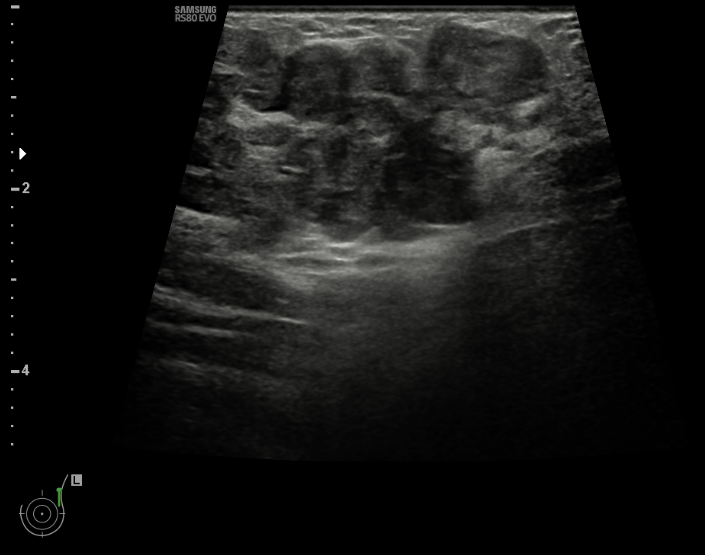

36 year old female comes with history of left breast lump. She is evaluated outside for same and HPR is papillary lesion. She comes to our hospital, we repeat her mammogram and USG, which is suggestive of a high density large mass with lobular margin in upper outer quadrant of left breast. As out side HPR is discordant with imaging finding, we repeat her biopsy and MRI. Repeat biopsy is suggestive of again papillary lesion. And MRI is suggestive of invasion of chest wall muscle. What do we do now?

Adenomyoepithelioma is a primary breast neoplasm of rare entity caused by proliferation of both epithelial and myoepithelial components, Benign to low grade malignant behavior and has a propensity for recurrence. Either epithelial or myoepithelial component can show malignant transformation so thorough evaluation recommended*. Overlap of histopathological features usually lead to misinterpretation as invasive carcinoma or intraductal papilloma or sclerosing adenosis. Complete wide excision with negative margins is standard treatment to prevent local recurrence. It is difficult to diagnose this on imaging alone, however familiarity with this rare entity to radiologist is essential to raise possibility.

Final histopathology was suggestive of Adenomyoepithelioma (AME). (Few foci of atypia were seen, however there was no malignancy)